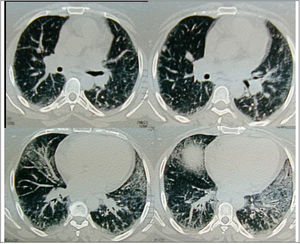

Regarding the regional distribution of abnormalities, reticular pattern and HC were the most common in the lower lung zones (Figs. 1 and 2).

Axial HRCT images at level 3 and 4 in a 38 year-old female show mixed reticular and GGO patterns as septal thickening in lung bases and limited patchy areas of GGO. This patient had FVC 61% of predicted value (mild restriction pulmonary impairment). A predominant reticular pattern and a coarseness grade of 3 were assigned.